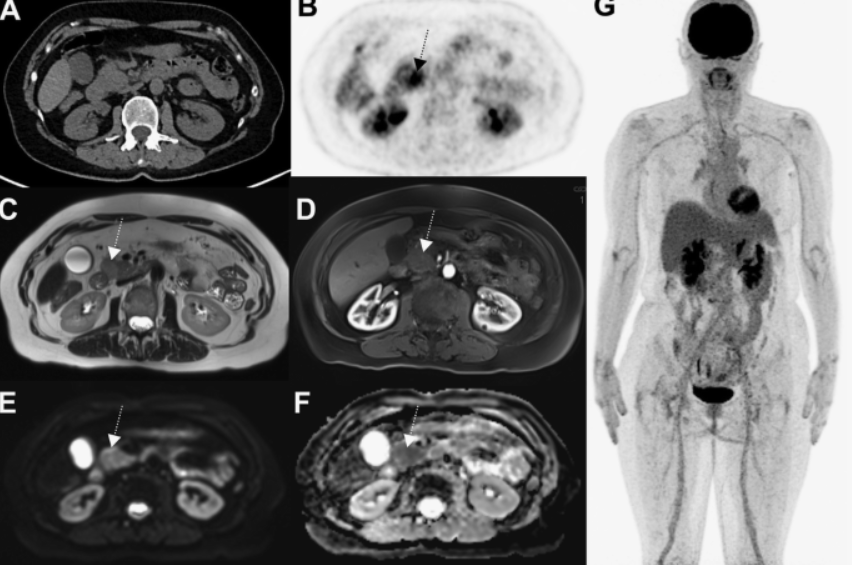

Магнитно-резонансная томография (МРТ):один из самых эффективных методов диагностики заболеваний